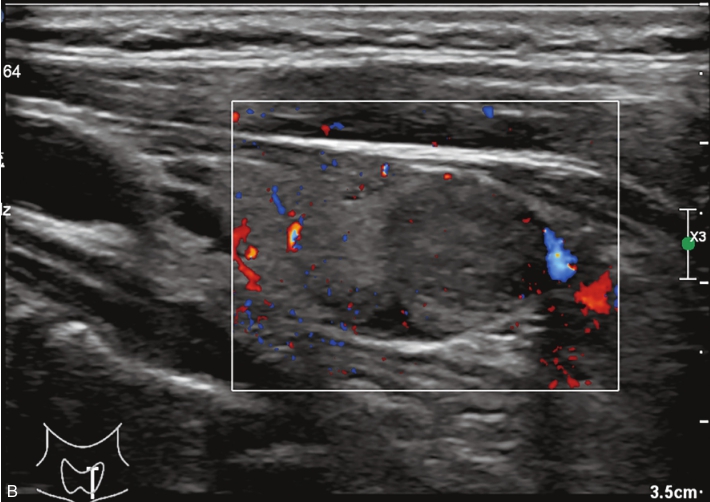

男性,64岁,体检发现甲状腺结节1天。体格检查:甲状腺无明显肿大。

甲状腺左叶中部实性中等回声,边缘光整,纵横比<1,内未见明显强回声,CDFI:结节内见血流信号,见图1-3-9。

图1-3-9 结节性甲状腺肿常规超声声像图

A.甲状腺左叶纵切面;B.CDFI血流图

甲状腺左叶中部结节15s开始增强。增强早期与周围正常甲状腺组织呈同步等增强,内部增强不均匀,增强后结节边界清,形态规则,周边可见环状高增强,增强晚期呈不均匀性低增强,见图1-3-10、ER1-3-5。

结节性甲状腺肿超声造影表现为病变多与周围正常甲状腺组织呈同步等或高增强,增强多较均匀,伴有囊性变者,内部可见无增强区,增强后结节边界清,周边可见环状增强,增强晚期呈等或稍高增强,也可呈稍低增强。

图1-3-10 结节性甲状腺肿超声造影图

A.增强早期结节呈同步不均匀性等增强;B.增强晚期呈不均匀性低增强